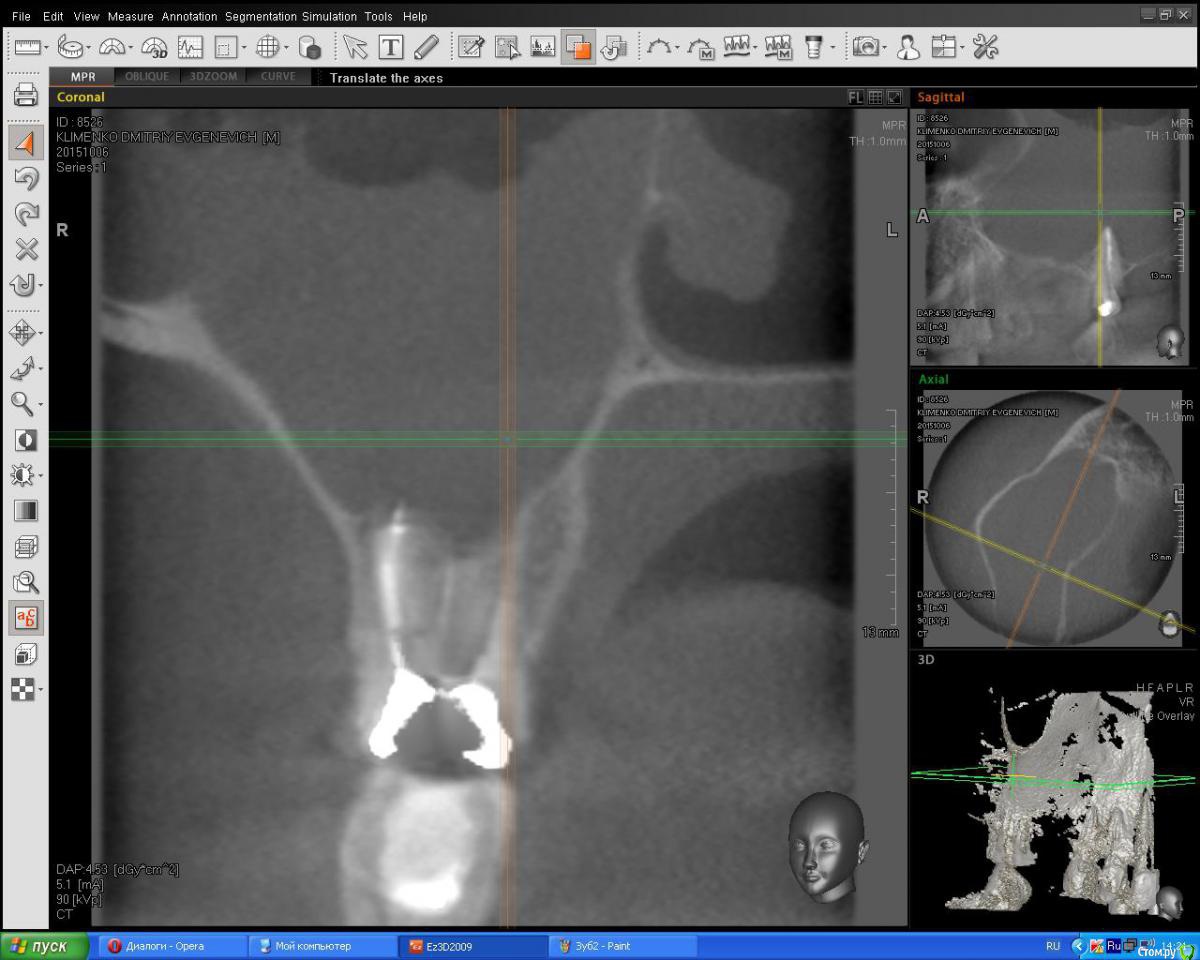

listopad19531 Опубликовано 11 октября, 2015 Поделиться Опубликовано 11 октября, 2015 Здравствуйте. Две недели назад мне перепломбировали каналы верхнего зуба (1-7, 7й справа). Ранее в зубе стояли штифты. Зуб начали готовить под коронку, штифты убрали и решили, что каналы лучше перелечить. После перепломбировки начался гайморит, сопровождаемый температурой 37,2, болями в виске и правом глазу, иногда боли отдаются в зуб. Антибиотики и лечение гайморита я провожу, но боли и температура остаются (это тянется 2 недели). Стоматолог говорит, что лечение выполнено качественно. ЛОР лечит гайморит и отправляет к стоматологу. И так далее... Выкладываю снимки. Вопрос. все ли в порядке с косточкой гайморовой пазухи? Не повреждена ли она? Продолжать ли лечить гайморит или перелечивать зуб? Возможно ли его теперь перелечить? Спасибо Ссылка на комментарий